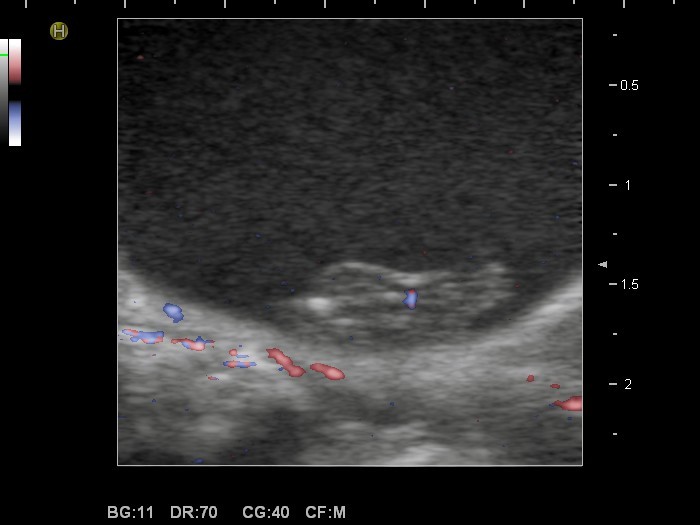

Follicular adenoma - Case 8. (ultrasonographic picture 9)

Left lobe, horizontal scan, color Doppler mode, fine flow method. Signs of perinodular blood flow.